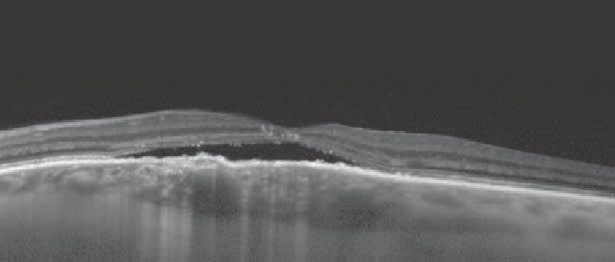

Patients who have been undergoing anti-VEGF therapy may develop something that looks like cysts or subretinal fluid on clinical examination. A closer look, using SD-OCT, may reveal what is really outer retinal tubulation (Figure 3), which is not helped with additional anti-VEGF therapy. Looking at the entire 3-D cube scan, particularly the Z plane view, will confirm this diagnosis.

Figure 3. This patient was treated with numerous anti-VEGF injections, and the question is whether additional injections are required. The circular spaces seen on this OCT image represent outer retinal tubulation and not cystoid macular edema. Outer retinal tubulation does not respond to anti-VEGF injections, and this patient can be watched.